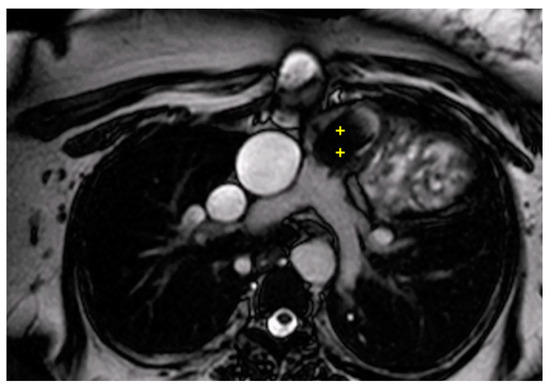

2.5. Evaluation of Coronary Anatomy and Stress Perfusion Imaging